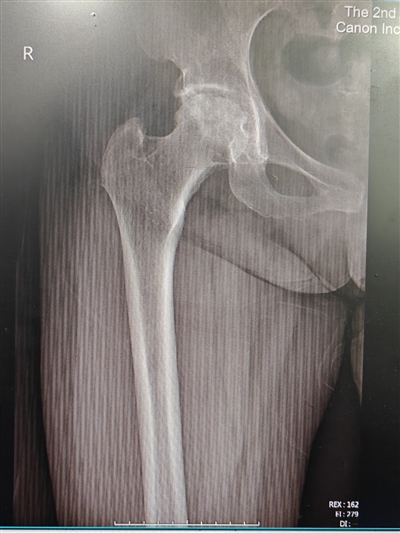

56岁的黎女士(化名)双侧髋关节反复疼痛、活动障碍一年多了,期间曾在多家医院就诊,但医生均拒绝为其进行手术治疗,保守药物对症治疗效果也不佳。由于疼痛剧烈、长期夜间无法入睡,黎女士逐渐产生了抑郁的情绪,甚至有了轻生的念头。在辗转求医的过程中,黎女士经朋友介绍,带着仅有的希望找到了重庆医科大学附属第二医院骨科—关节外科中心的李锐冬副主任医师,李锐冬副主任医师仔细询问病史后,发现黎女士因患有皮肌炎长期使用激素,结合影像学检查,确定黎女士为双侧股骨头坏死。

李锐冬副主任医师团队立即对黎女士进行了全面的检查,发现其双侧髋关节病变均较为严重,需进行全髋关节置换。传统的后外侧入路切口比较长,考虑到患者本身肥胖,且有皮肌炎病病史,传统入路更易导致脂肪液化、伤口愈合不良等问题,结合到患者希望术后康复周期尽量短等意愿,李锐冬副主任医师团队在经过严密的讨论、多学科会诊及与患者仔细的沟通后,决定对黎女士行创伤更小、康复更快的DAA全髋关节置换术。

术前X片